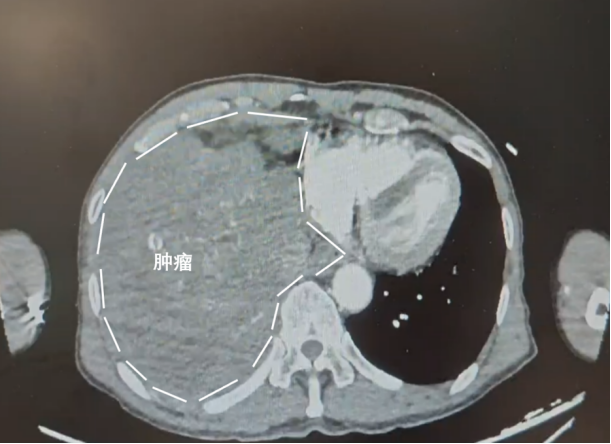

黄叔右侧胸腔存在一个巨大的肿瘤,几乎占据了整个右侧胸腔,仅余少量的右肺组织在艰难维持生命。

[ 白色虚线处为黄叔的肿瘤 ]

而且还远远不止肿瘤,黄叔的肝内,还同时存在钙化灶和右肾多发结石等问题。

*黄叔穿刺病理结果为(右胸腔占位)间叶源性肿瘤,结合免疫组化,倾向低度恶性梭形细胞肿瘤。